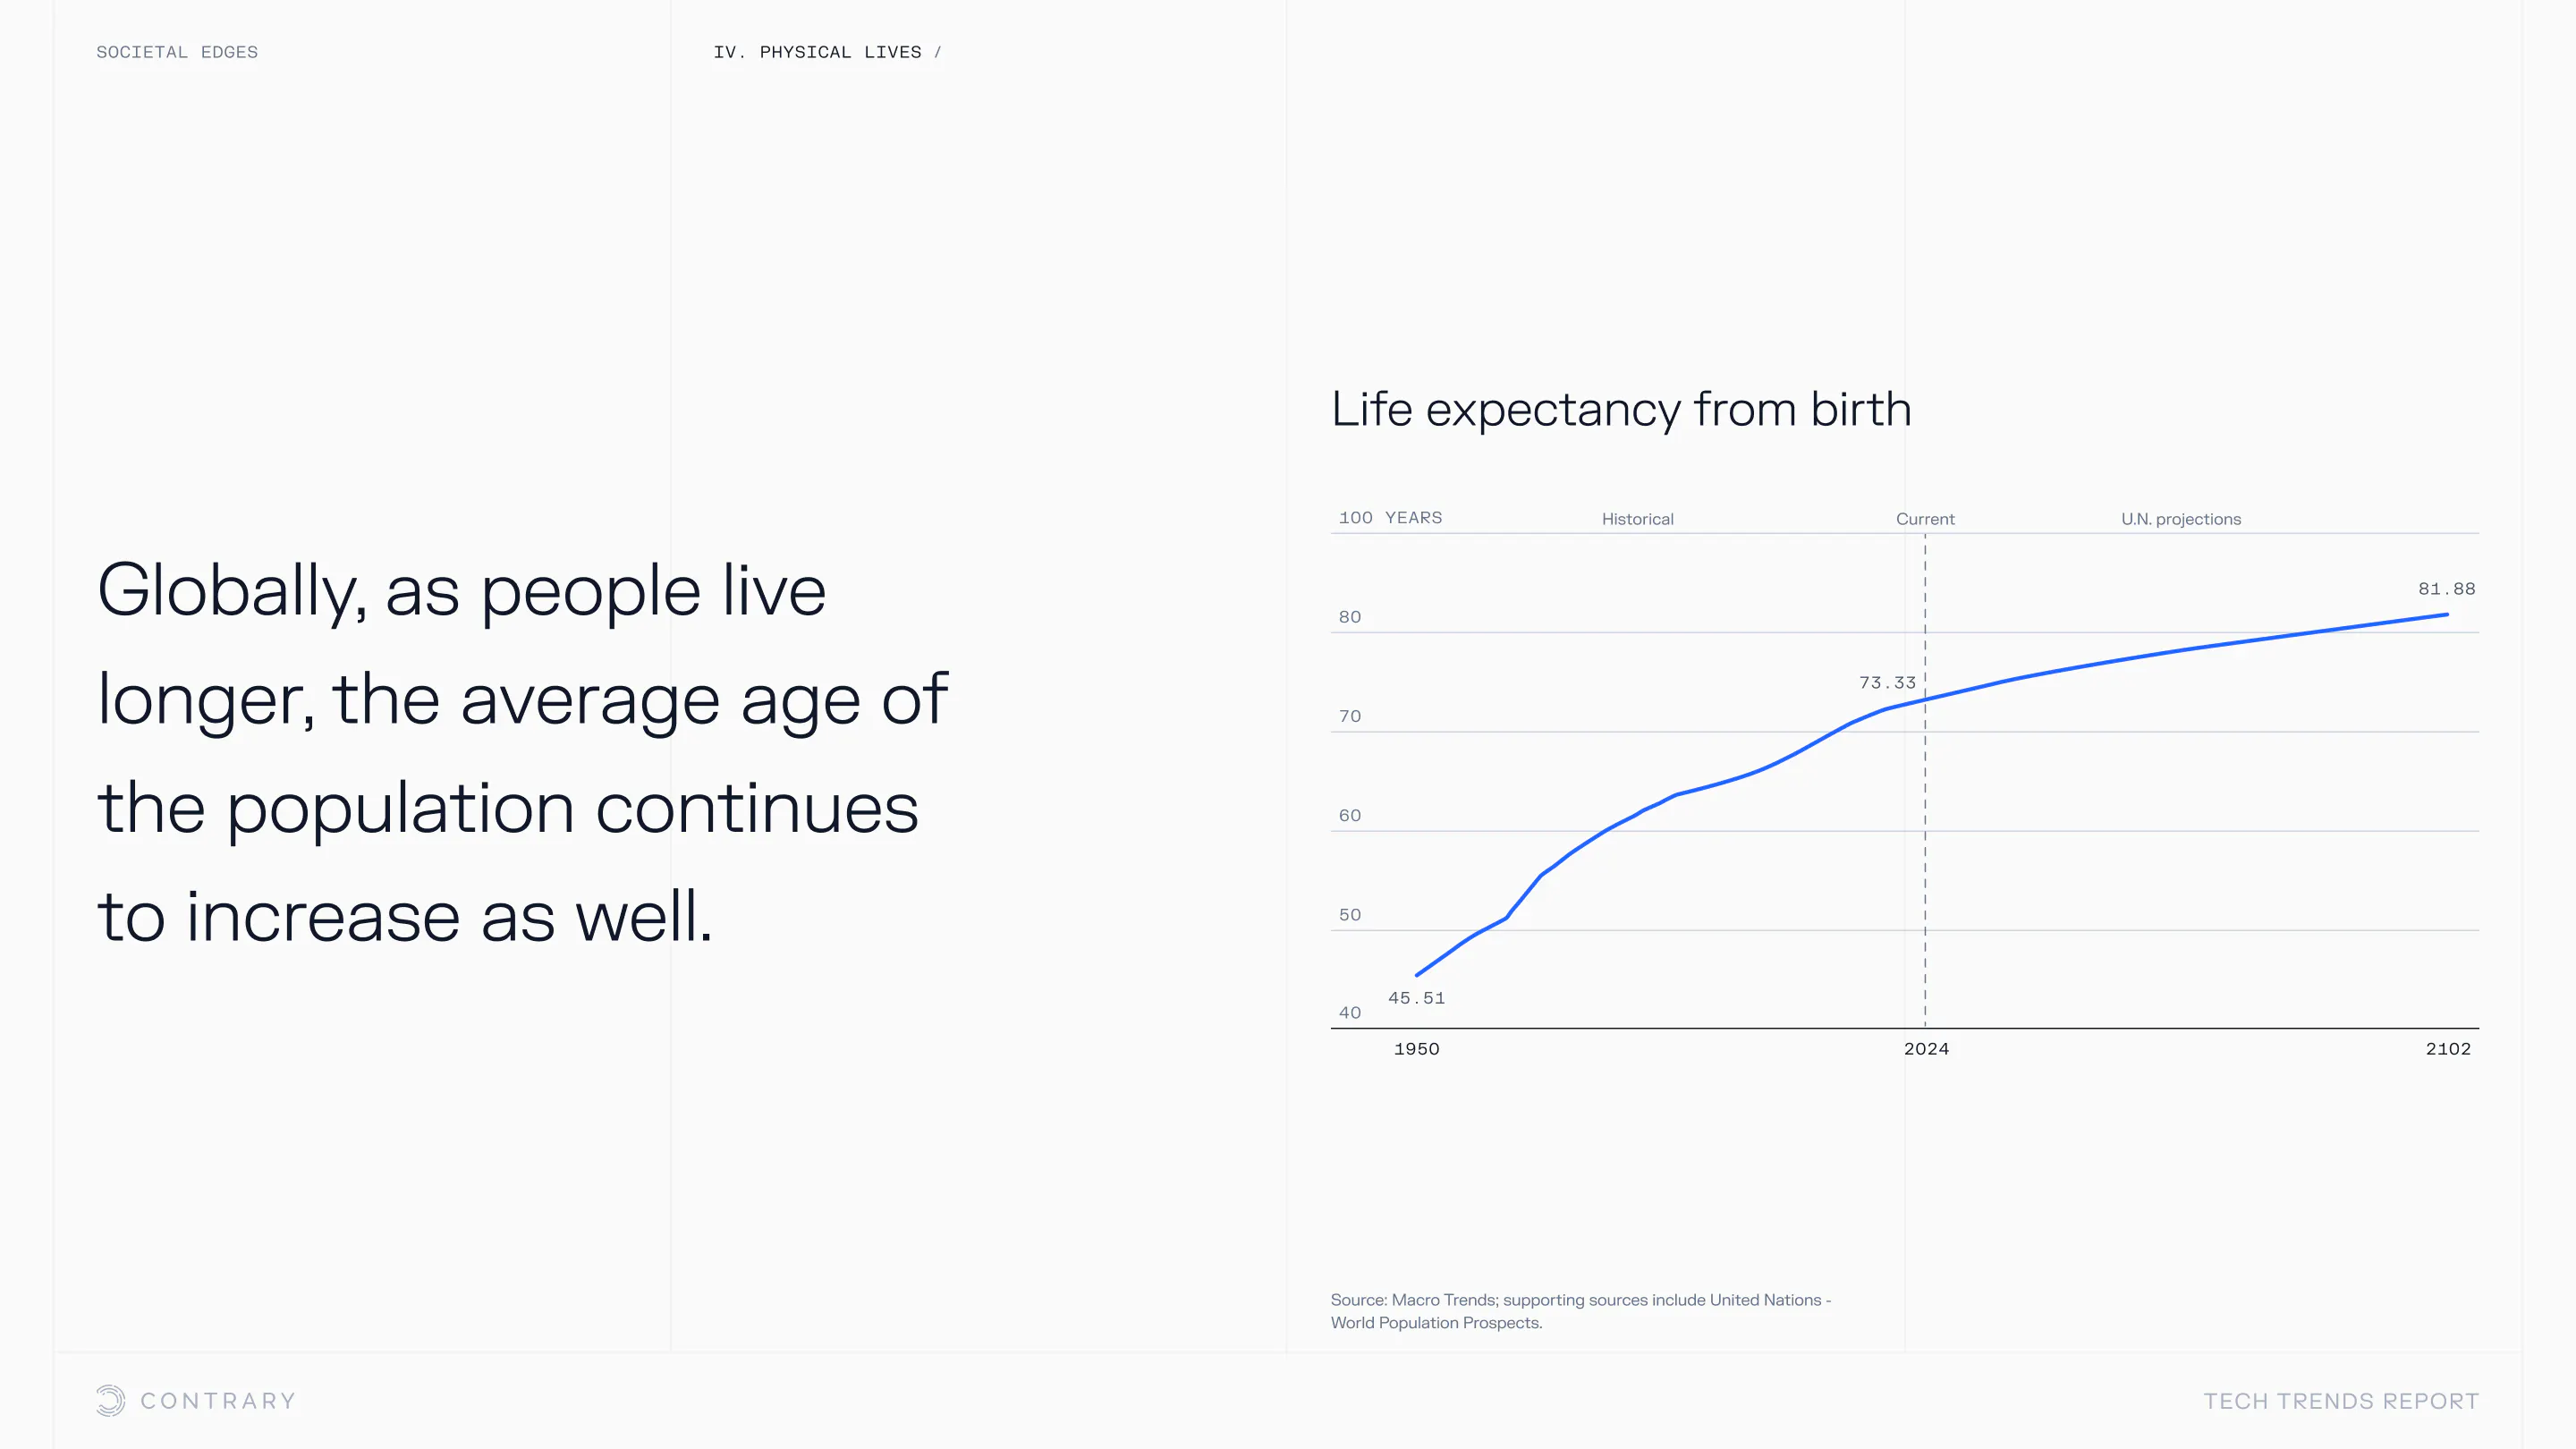

An aging population is bringing up a range of increased concerns, from mental health to disease control. Obesity and gastrointestinal cancers are plaguing younger generations. The cutting edge is tackling a system that has unhealthiness woven into it.